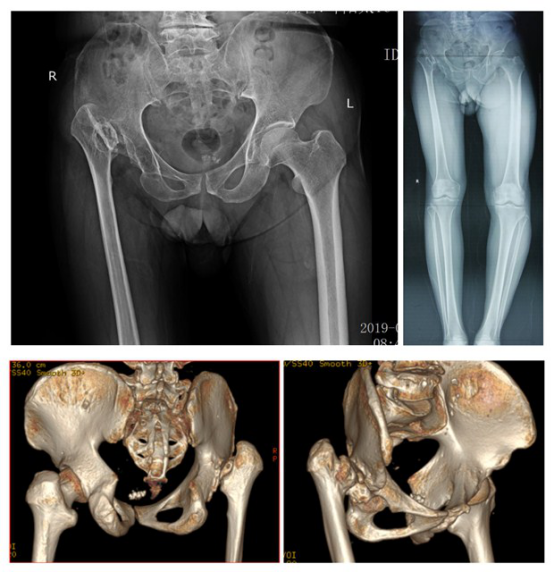

惠州三院關(guān)節(jié)外科崔鳳金主任在會(huì)議上與其他會(huì)場(chǎng)專(zhuān)家分享了一例手術(shù)難度極高的病例,患者為64歲男性,主因是“右髖疼痛2年、加重半年多”入院治療。崔主任以患者現(xiàn)病史、既往史、體格檢查、x光片、CT、MR檢查等各項(xiàng)內(nèi)容為依據(jù),診斷患者是“右側(cè)髖關(guān)節(jié)發(fā)育不良”,并把手術(shù)方案分享給各大會(huì)場(chǎng)教授進(jìn)行點(diǎn)評(píng)。各會(huì)場(chǎng)教授對(duì)于惠州三院提出的特殊病例紛紛提出了自己的看法和建議,對(duì)病例的多種可能性進(jìn)行討論,意見(jiàn)紛呈,現(xiàn)場(chǎng)氣氛高漲。

手術(shù)前

手術(shù)后

這是一例四度DDH的患者。這類(lèi)患者施行全髖關(guān)節(jié)置換手術(shù),是骨科帶有標(biāo)志性意義的高難度手術(shù)之一?;葜萑宏P(guān)節(jié)外科專(zhuān)家經(jīng)過(guò)術(shù)前認(rèn)真討論和規(guī)劃,順利地為患者實(shí)施了手術(shù),術(shù)后患者如期下地行走,解決了困擾患者多年的髖部疼痛和跛行的問(wèn)題。近年來(lái),隨著骨科技術(shù)水平的不斷提高,社會(huì)影響力越來(lái)越大,越來(lái)越多的骨科患者來(lái)這里求醫(yī)。一臺(tái)臺(tái)精準(zhǔn)的手術(shù),為一個(gè)個(gè)長(zhǎng)期受病痛困擾的家庭帶來(lái)曙光。